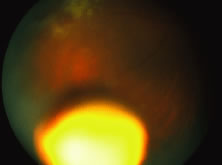

A variable number of eyes, up to 75%, develop retinal detachments (Fig. 5). Prophylactic laser for demarcating the areas of active retinitis from normal retina has been advocated to create chorioretinal adhesions that prevent retinal detachments around sites of retinal break formation (which usually occur at the zone between affected and healthy retina). Han and associates43 reported five cases treated with prophylactic laserpexy in addition to antiviral, steroid, and antiplatelet therapy. After 15 months of follow-up, no retinal detachments were noted. Sternberg and coworkers44 described a 75% decrease in the rate of retinal detachment using prophylactic photocoagulation. Some have advocated the creation of a “new ora serrata” by applying confluent rows of laser burns posterior to the areas of retinitis. However, if traction forces from vitreous organization, epiretinal membrane (ERM) formation, or proliferative vitreoretinopathy develop as they commonly do, the contractile forces will be able to overcome any increased chorioretinal adhesion created by the laserpexy. However, McDonald and associates45 reported failure of prophylactic peripheral laserpexy to prevent retinal detachment in ARN patients. In addition, many cases of ARN result in a severe vitritis, limiting the view for a planned laserpexy (Fig. 6). Therefore, vitrectomy with endolaser and concomitant encircling of the eye with a scleral buckle to reduce traction may be required in some patients.46,47 Decisions relating to the need for scleral buckling to support retinal breaks and the use of silicone oil or long-acting gases to repair retinal detachments should be made by an experienced vitreoretinal surgeon.40,48 Selection of cases to undergo operation should be made with consideration given to optic nerve function, visual potential, and medical control of retinitis.

Fig. 5. A patient with funnel-shaped retinal detachment and proliferative vitreoretinopathy complicating acute retinal necrosis syndrome.